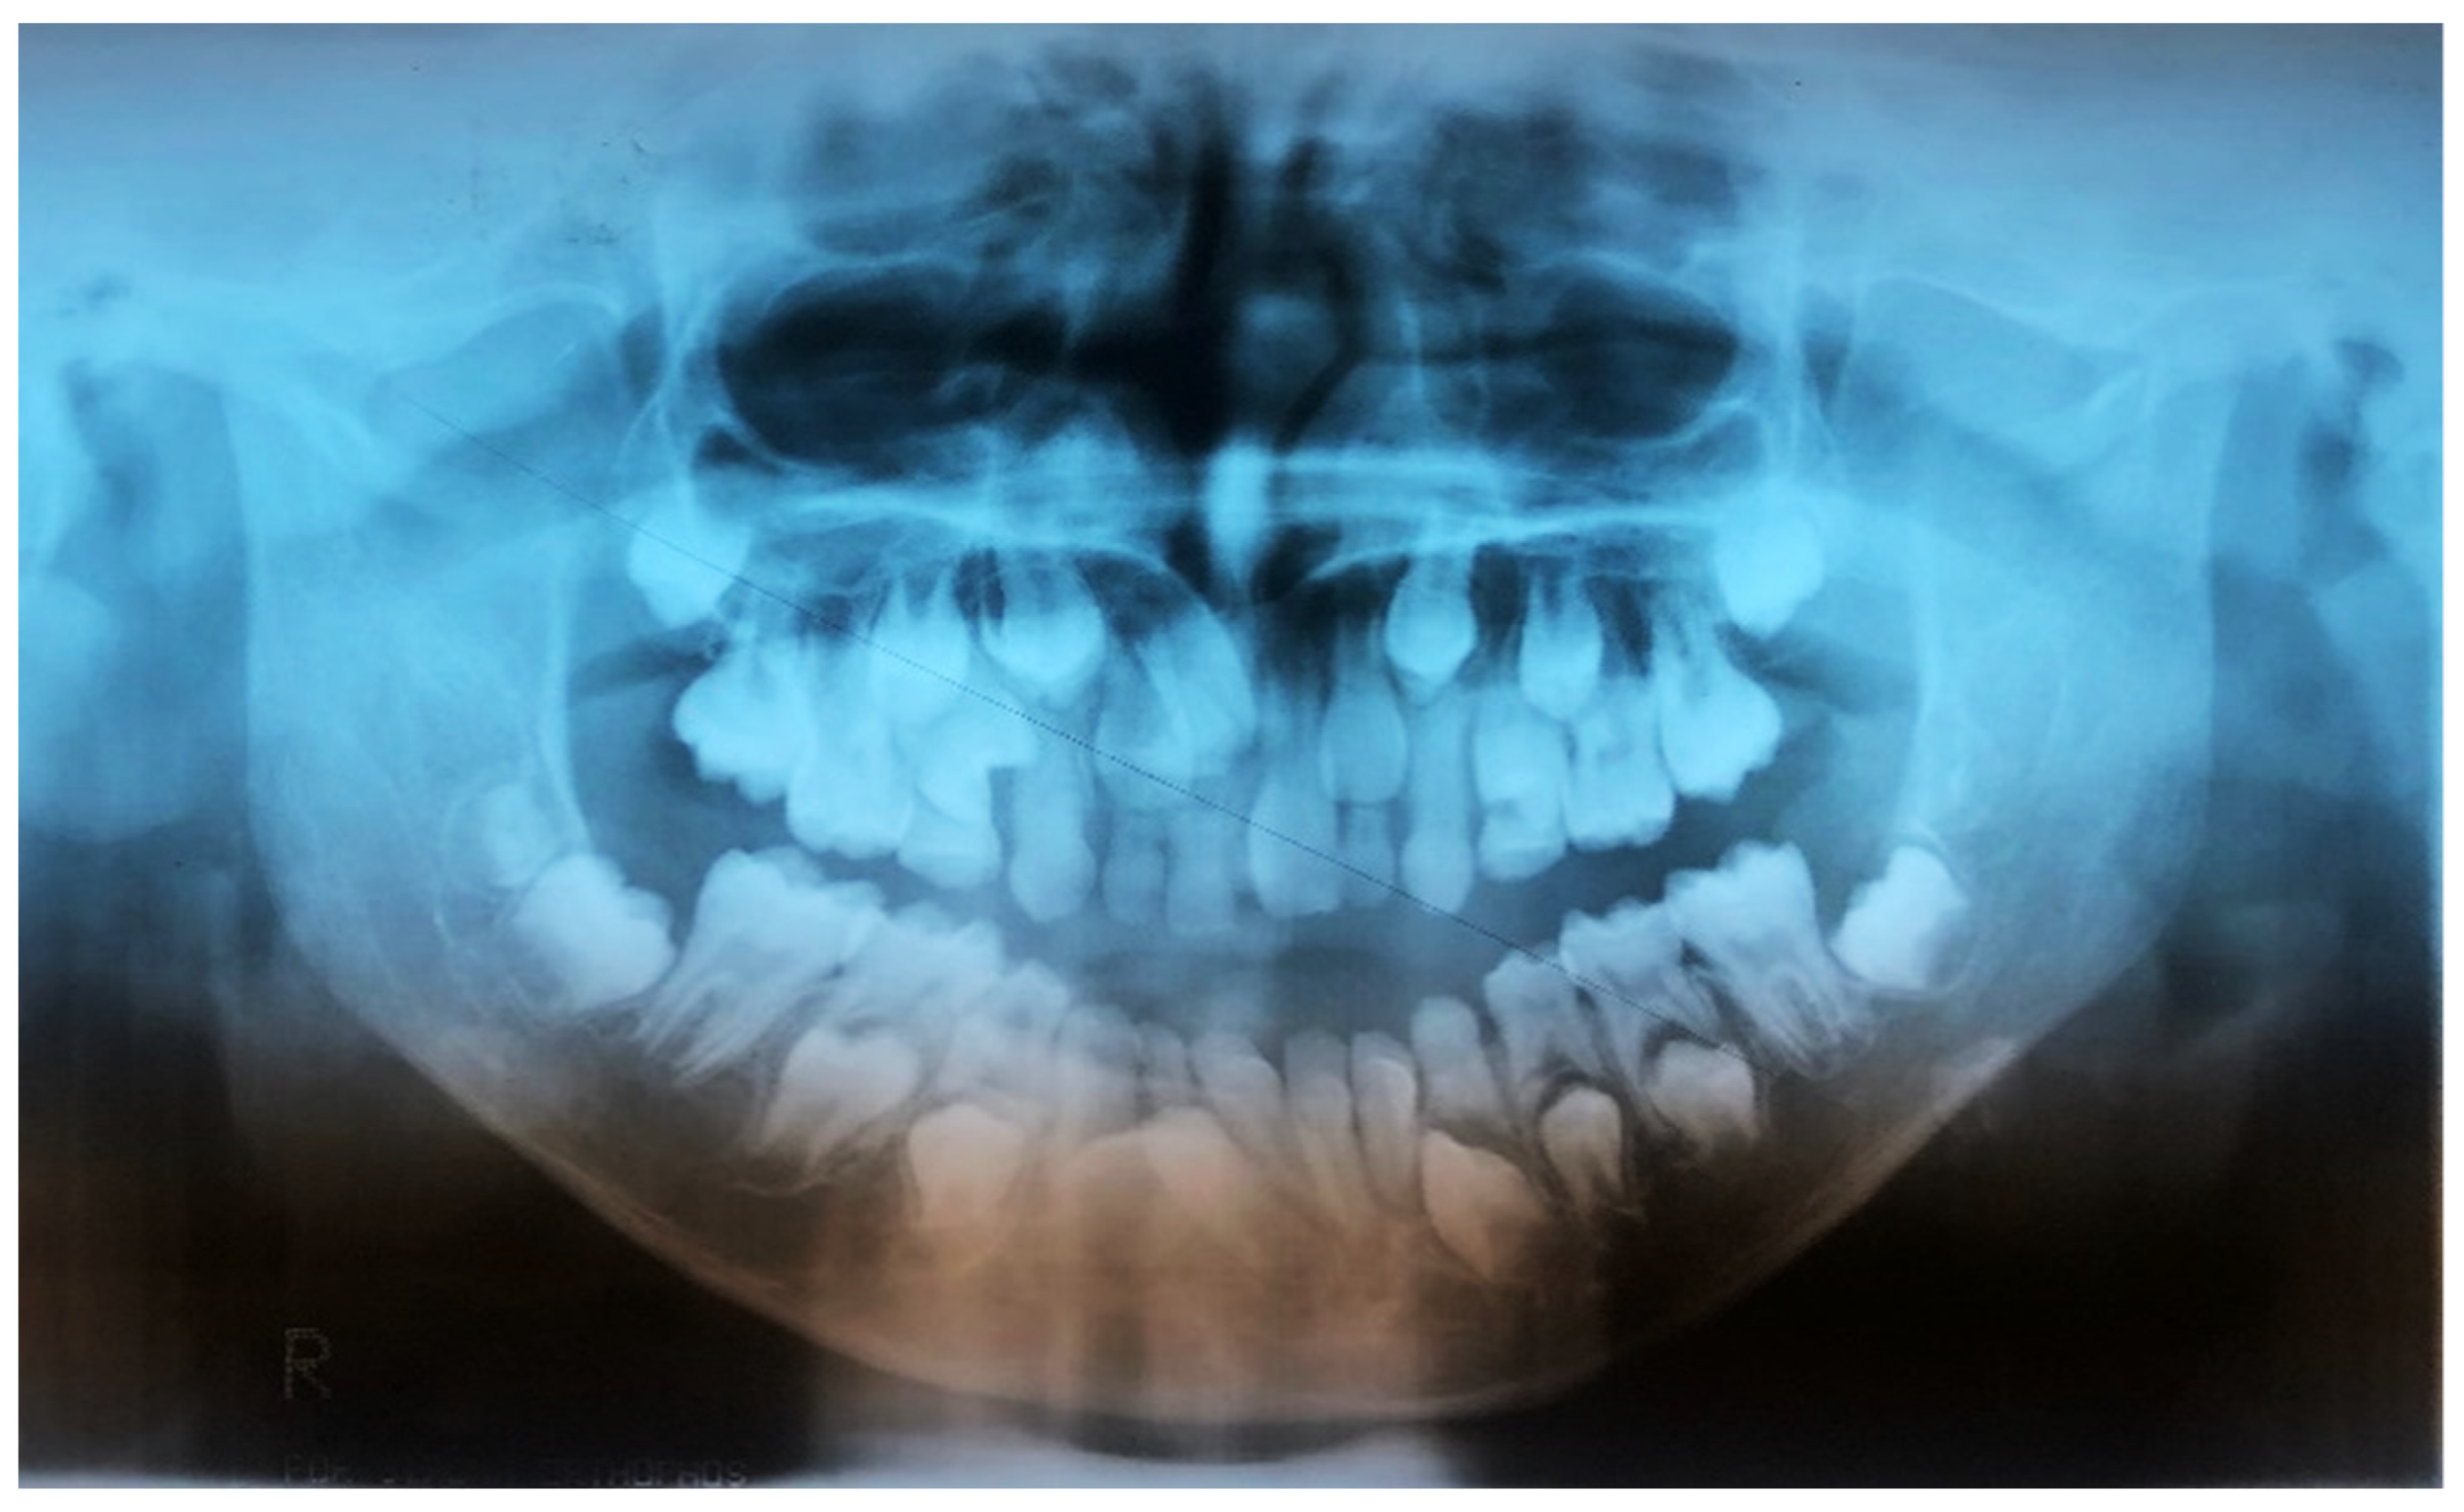

2.2. Considerations for Supranumerary Teeth Extraction